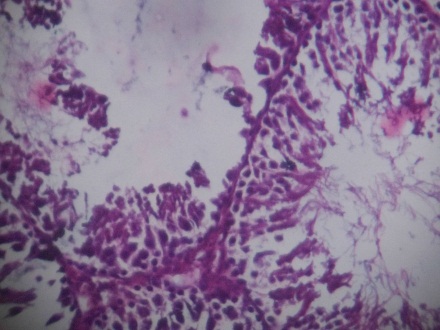

The bone marrow of Rasa Mezhugu treated rats (high/low/Middle dose) found within the central cavities of with hematopoietic tissue islands and adipose cells surrounded by vascular sinuses interspersed within a meshwork of bone (fig. 8-10). The cerebrum showed the absence of neuronal degeneration, edema and gliosis (fig. 11-13). The Cardiac muscle revealed normal appearances of the centrally arranged nucleus, connective tissue with distinct cardiac muscle fibers were well arranged (fig. 14-16). The kidney shows no glomerular or vascular injury the bowman's capsule with distinct polymorphonuclear cell nuclei with normal cells of renal cortex (fig. 17-19). The liver cells showed the normal microscopic architecture of the liver with hexagonal lobules and acini with the distinct central vein, portal triad, portal vein and hepatic artery with parenchyma cells (fig. 20-22). The lungs photos revealed that normal cytoarchitectural with predominant smooth muscle layer of the bronchi with enlargement of the alveoli and the alveoli sacs (fig. 23-25). The pancreas with normal acinar cells arranged in lobules with prominent nuclei. The islet cells are embedded within the acinar cells and surrounded by a fine capsule with normal histological structure (fig. 26-28). The spleen showed no changes congestion, hemorrhage, edema, and erosions the cells are a clear and proper arrangement (fig. 29-31). Photomicrograph of stomach mucosal layer has shown normal cells with distinct mucosa, submucosa, muscle layers and serosal layers showing normal architecture (fig. 32-34). The tests of rat’s revealed normal architecture with normal germinal epithelium, fully mature sperms filled the lumen of seminiferous tubules with tubular epithelium cells, absences of vascular congestion/interstitial edema and degenerated cells (fig. 35-37).

| Fig. 19: Histopathology slide photos of Rasa Mezhugu-High dose treated animals’ Lungs | Fig. 20: Histopathology slide photos of Rasa Mezhugu-Low dose treated animals’ Lungs | Fig. 21: Histopathology slide photos of Rasa Mezhugu-Middle dose treated animals’ Lungs |

| Fig. 22: Histopathology slide photos of Rasa Mezhugu-High dose treated animals’ Pancreas | Fig. 23: Histopathology slide photos of Rasa Mezhugu-Low dose treated animals’ Pancreas | Fig. 24: Histopathology slide photos of Rasa Mezhugu-Middle dose treated animals’ Pancreas |

| Fig. 25: Histopathology slide photos of Rasa Mezhugu-High dose treated animals’ Spleen | Fig. 26: Histopathology slide photos of Rasa Mezhugu-Low dose treated animals’ Spleen | Fig. 27: Histopathology slide photos of Rasa Mezhugu-Middle dose treated animals’ Spleen |